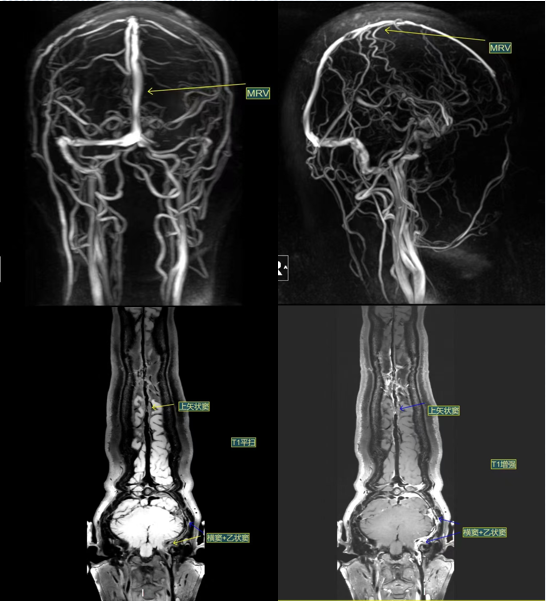

影像表现:

左侧横窦、乙状窦管壁弥漫增厚伴斑块形成,增强明显强化,管腔重度狭窄;上矢状窦管壁弥漫增厚伴局部斑块形成,管壁明显强化,管腔局部重度狭窄。

这些影像表现,清晰地指向了“静脉窦狭窄”这一诊断。静脉窦是脑内静脉血回流的“主干道”,一旦狭窄,血流受阻,就会导致颅内压力升高,进而引发头痛、视力下降、耳鸣等一系列症状。

在这位患者的影像中,不仅看到了“管腔狭窄”,更看到了“管壁增厚+斑块形成”,这说明狭窄并非先天结构异常,而是后天病理改变所致。这种信息对于治疗方案的选择至关重要。